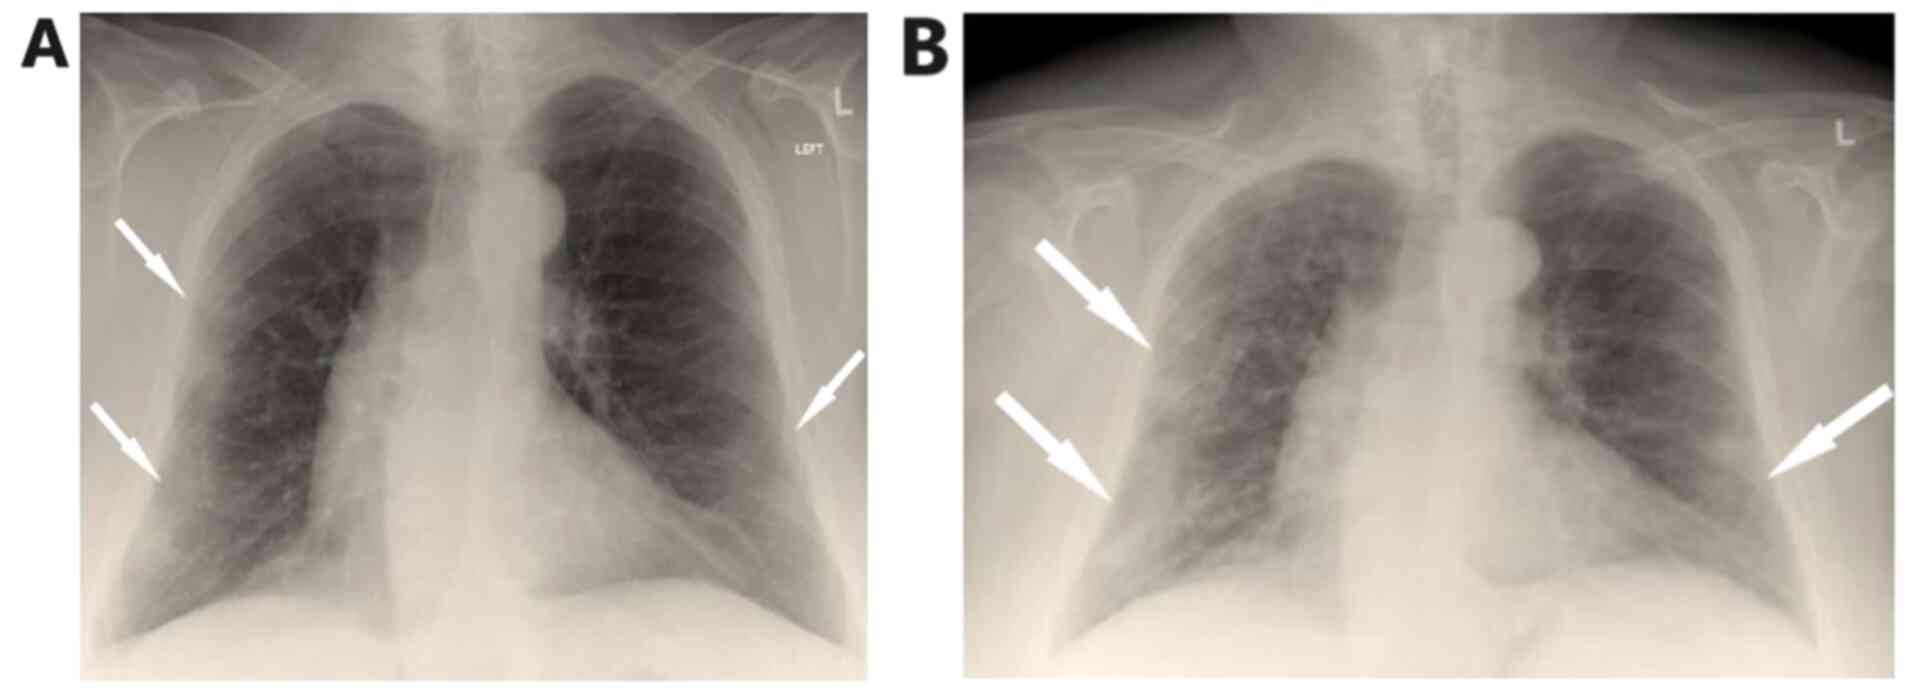

Arterial blood gas analysis showed pO2 52 mmHg, pCO2 32 mmHg, pH 7.53 and HCO3 26.7 mmol/l on room air. Chest X-Ray showed patchy diffuse infiltrates in both lungs mostly in the periphery of the left lung (Fig. 1A).

Figure 1

(A) On admission, chest X-ray shows bilateral lung infiltrates, mostly in the periphery of the left lung. (B) Chest X-ray on the 5th day shows worsening of infiltrates.

On the fifth day of hospitalization, fever reoccurred and the patient presented with worsening cough with green sputum, with reduction in partial pressure of oxygen, changes in findings from lung auscultation with rhonchi sounds found in all lung fields and worsening infiltrates on chest X-ray (Fig. 1B). The patient received oxygen with Venturi mask delivering 50% oxygen and intravenous piperacillin-tazobactam empirically. She underwent high resolution computed tomography of the chest showing bronchiectasis and nodular ground glass opacifications mostly with peripheral and subpleural distribution in both lungs (Fig. 2A-C).